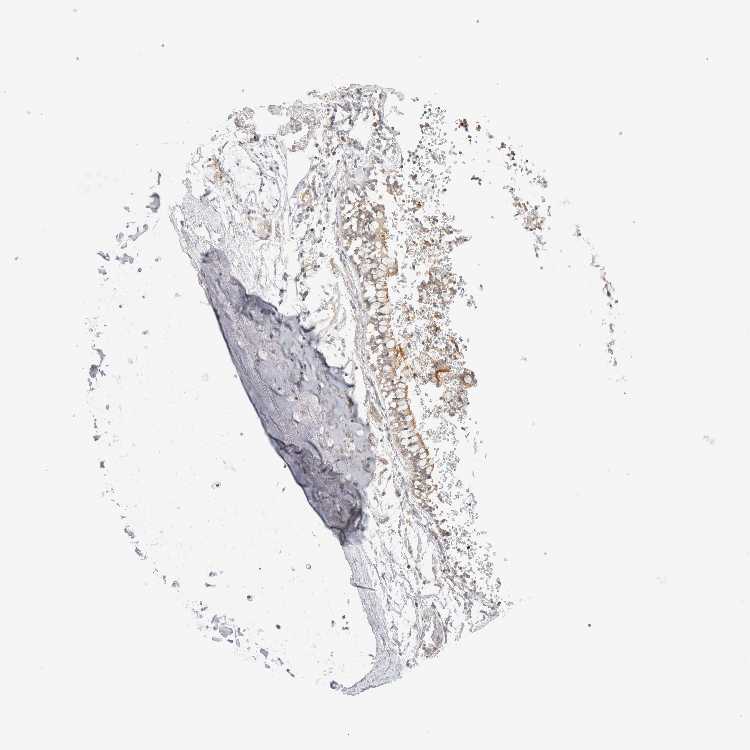

SOFT TISSUE 1 - Antibody stainingi

Antibody staining in the annotated cell types in the current human tissue is reported as not detected, low, medium, or high, based on conventional immunohistochemistry profiling in selected tissues. This score is based on the combination of the staining intensity and fraction of stained cells.

Each image is clickable and will lead to virtual microscopy that enables deeper exploration of all samples and also displays staining intensity scores, fraction scores and subcellular localization as well as patient and tissue information for each sample.

Antibody HPA024652

Chondrocytes Not detected

Fibroblasts Not detected

SOFT TISSUE 2 - Antibody stainingi

Peripheral nerve Not detected